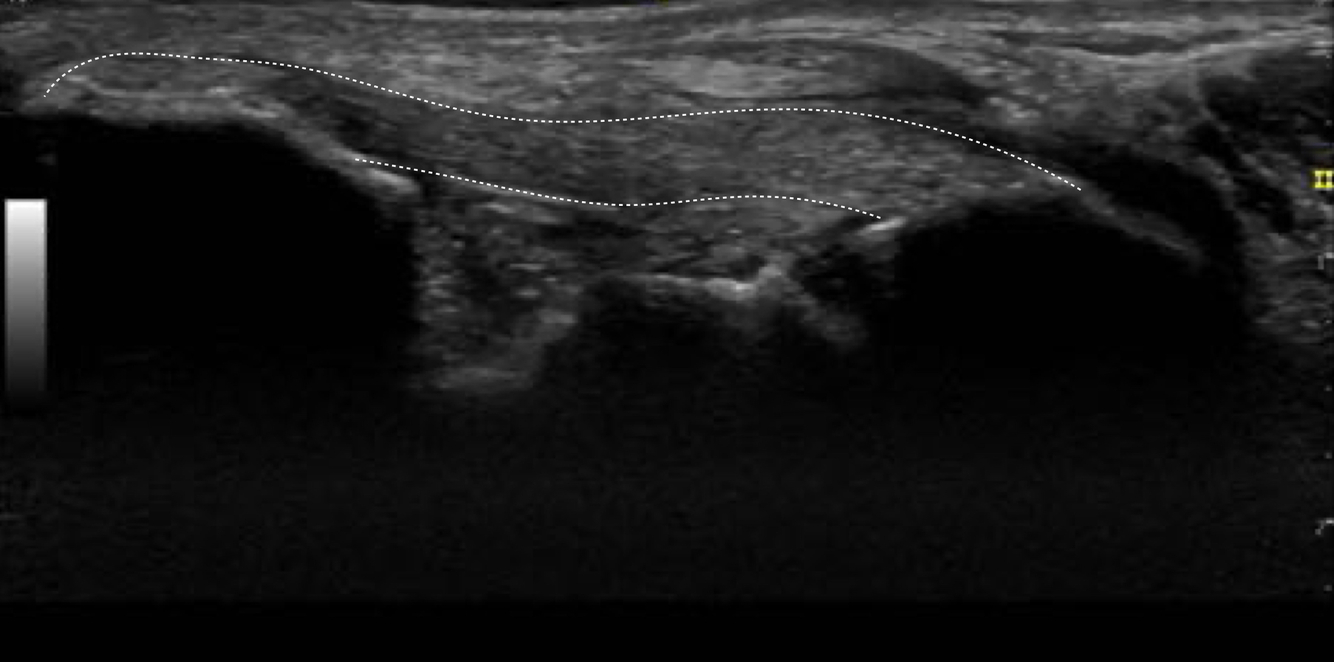

Q

Identifie les structure sur l’image

Dites dans quelle region du pied il se situe

A

Région du long fibulaire en long axe, donc sous le pied